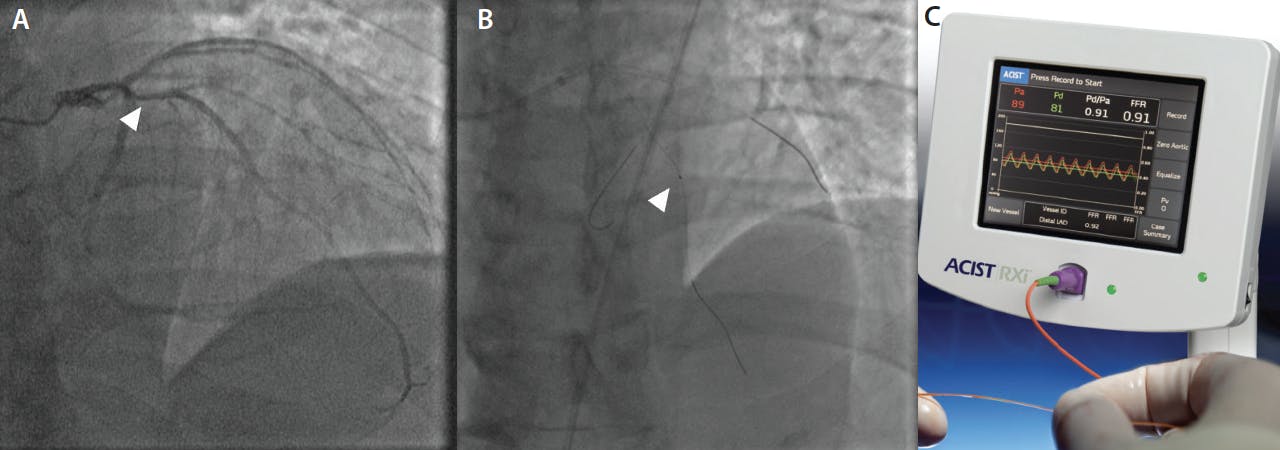

When angiographically ambiguous lesions are present, adjunctive tests such as coronary physiology are used to further assess lesion severity (Figure 3). The Navvus II® Rapid Exchange FFR microcatheter (ACIST Medical Systems) is an elegant way to perform physiological assessment in ambiguous lesions because the microcatheter may be used with a standard workhorse wire, with potential safety advantages over other wire-based physiology devices, such as wire-induced dissection and inadvertent passage into small vessels.

Figure 3. Ultra-low contrast invasive coronary physiology to eliminate diagnostic ambiguity. A patient with advanced CKD (GFR 8 mL/min) underwent ULCA with contrast dilution showing an ambiguous lesion in the proximal left anterior descending coronary artery (arrow) (A). Invasive coronary physiology is performed with the Navvus II microcatheter (B), without contrast guidance, confirming the absence of ischemia (C).